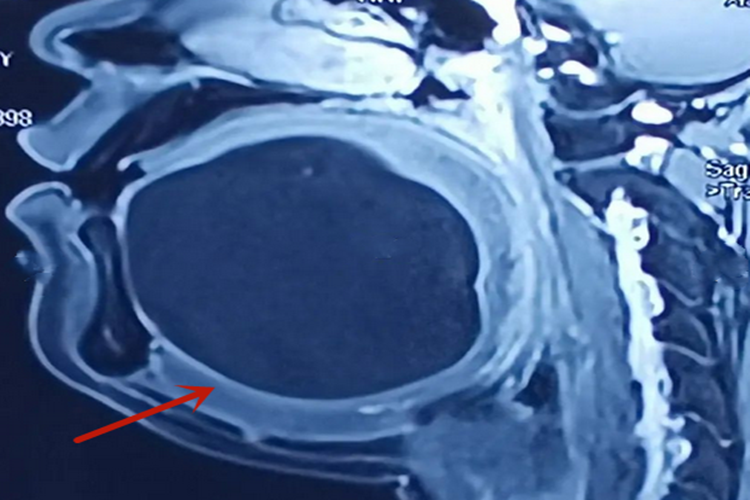

皮样囊肿:因生长缓慢,早期多不显症状,可能表现为圆形或椭圆形,表面光滑,无痛性肿块,边界清楚,有面团感,肿块不可压缩,不随体位改变而增大或缩小。